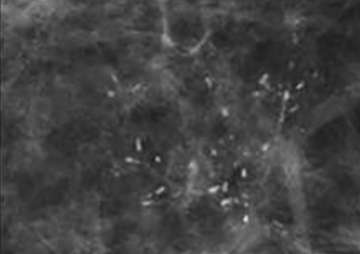

Fine Linear Calcifications

Fine linear or fine linear branching: thin, linear and usually discontinuous calcifications which represent calcified necrotic debris within a duct compromised by carcinoma. When these calcifications are new and present in a segmental distribution, they are considered a BIRADS 5 category finding.